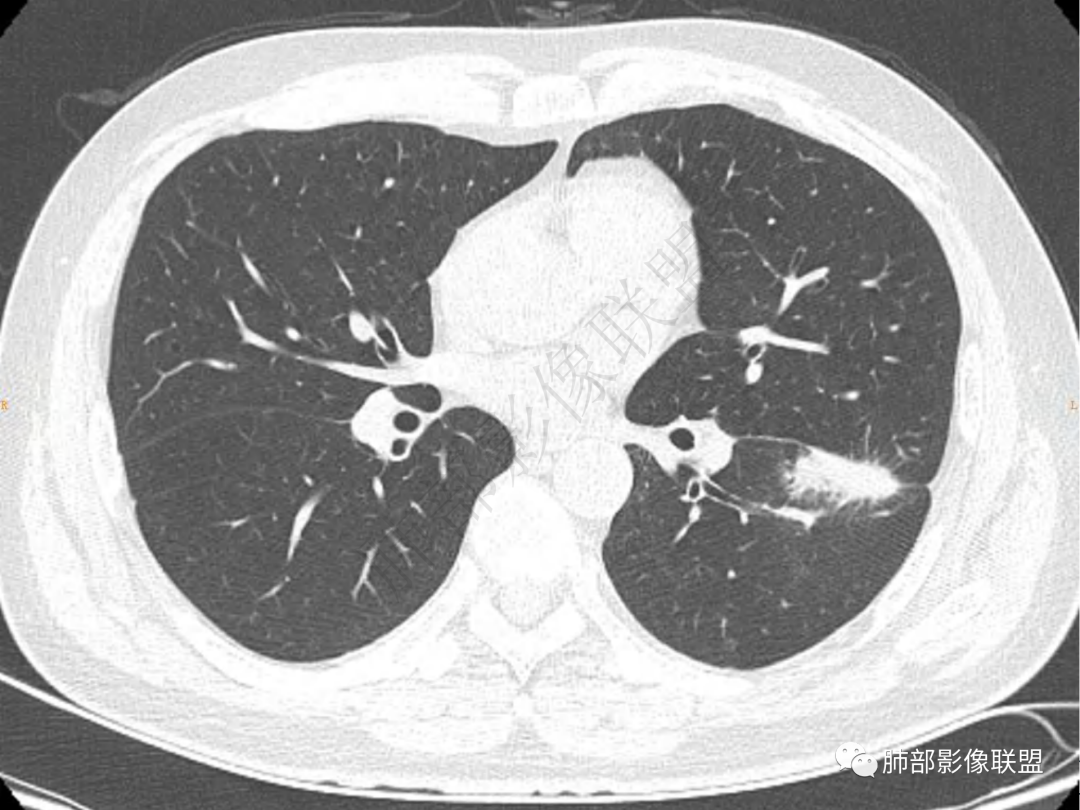

左肺下叶团片状高密度影,边缘尚清,短粗毛刺,其内看见支气管深入,呈空气征,多发小气道壁稍厚。病变未跨越胸膜裂,相邻胸膜裂未见明显牵拉,轻度膨隆,相邻纹理轻度牵拉增粗密度增高,肺野周围斑片状稍高密度影。结合临床,考虑感染可能性大。

左肺下叶前内基底段肿块,跨叶,边缘不清,周围散在磨玻璃密度影,偏下方支气管壁增厚,腔内偏一侧增厚,腔狭窄(痰栓?炎性?),纵隔窗纵隔内见空洞(似乎近背侧方向,治疗后?),中年男性,抗炎治疗后有效,考虑炎性,建议继续抗炎治疗后复查

中老年男性,左肺下叶团块,病灶与叶间胸膜相贴,边缘欠清晰,下方支气管扩张,抗炎治疗病灶有缩小,考虑炎性病变。

中年男性,中等病程,咳嗽,咳浓痰,左肺下叶类圆形实变,长毛刺,边界模糊,夜间裂未受累,无胸膜凹陷,无气管截断,考虑炎性病变。

男,51咳嗽咳痰20余天,间断咳血2周,左肺下叶叶间胸膜处见病灶影,边缘模糊,并见少许短毛刺,叶间胸膜轻度膨隆,考虑炎性病变可能,除外腺癌。

中年男性患者,咳嗽、咳痰20天,咳血2周,炎性指标正常,胸部CT:左肺下叶前基底段近斜裂处不规则斑片实变影,边界清楚,部分平直,部分彭隆,周边见界限清楚的磨玻璃影,分叶不明显,毛刺细软,内部密度不均匀,支气管有牵拉性扩张,首先考虑炎性病变,腺癌待排

中年男性患者,咳嗽、咳痰20天,咳血2周,炎性指标正常,胸部CT:左肺下叶前基底段结节影,边界清楚,部分平直,部分彭隆,周边见界限清楚的磨玻璃影,分叶不明显,毛刺细软,强化均匀,周围见多发斑片状磨玻璃样密度影,首先考虑炎性病变

中年男性,无诱因咳嗽脓痰,而且不发热,后期出现咯血,而且抗感染后似乎有效,吸入?没有特殊宿主因素。亚急性病程,化脓菌感染暂时不考虑,病毒病史影像不支持。影像,左肺下叶靠近斜裂一斑块影,边缘平直收缩,周围多发小斑片影?上叶胸膜下有小结节影,支气管通畅,壁厚,胸膜增厚似乎侵犯至上叶,斑块有轻度坏死,未形成空洞,纵隔肺门淋巴结无肿大。考虑肉芽肿性病变,结核?其他?非特异性感染?

左肺下叶团状实性密度为主病灶,边缘模糊,整体彭隆部分平直边,有软毛刺,与叶间胸膜宽基底相连,感觉部分层面突破叶间胸膜(跨裂?)且叶间胸膜明显增厚,而且有结节感;病灶周围见磨玻璃影及小结节感;与侧胸膜可见小梭形相连(是否淋巴道水肿改变)。支气管自然穿行,管壁未见明显增厚。增强后实性范围变小,相对均匀中等强化。未见明确肿大淋巴结。首次遇到基本考虑炎性病灶,治疗两周复查,鉴别腺癌。

中年男性,亚急性病程,咳嗽咳痰,左肺下叶团块影,内见支气管充气征,边缘平直、凹陷,周围见模糊GGO,明显强化,考虑炎性病变

男,51岁,咳嗽咳痰就诊,咳黄脓痰,治疗后咯血,左肺下叶叶间胸膜下团块影,宽基底与斜裂相连,周边伴磨玻璃影及条索影,平扫密度均匀,支气管扩张,增强可见强化,首先考虑为炎性病变,鉴别淋巴瘤

左肺下叶前内基底段团块影,周围见淡片状渗出,部分边缘清晰光整,相邻叶间裂局部增厚,其内似见液化坏死,纵隔窗前后变化较大(未提供两次CT间隔时间),病变缩小内见空洞,内壁光整。考虑炎性病变,脓肿?隐球?结核?

中年男性,咳嗽咳痰20天,咳黄脓痰,伴咯血,,左肺下叶靠近叶间裂处团片实变影,边缘平直为主,稍膨隆,边缘毛糙,支气管通畅,周围有磨玻璃及小斑片状影,内有坏死,边界欠清,有空洞,考虑感染性病变,肺脓肿,结核等,鉴别肺癌,以鳞癌,大细胞癌等。

左肺下叶前基底段肿块影,边缘平直为主,稍膨隆,有分叶毛刺,支气管通畅,周围有磨玻璃及小斑片状影,内有坏死空洞,边界欠清,与叶间胸膜宽基底相贴,考虑炎性肉芽肿性病变,鉴别淋巴瘤

左下肺肿块,边界不清,可见晕征及软毛刺,紧貼叶间胸膜但胸膜无牵拉移位,引流支气管管壁增厚,结节内有支气管穿行,显著强化,并见血管飘浮,纵隔窗肿块有平直及u型凹陷,综和考虑1.隐球菌,2.OP併脓肿,3.病史长,年龄大,淋巴瘤也要排除

1.中年男性,咳嗽咳痰20余天,间断咯血2周

2.左肺下叶团片影,跨背段及内前基底段,实性部分类椭圆形,密度不甚均匀,可见毛刺及棘状突起,未见典型分叶及胸膜凹陷。病灶上下缘可见相应肺段支气管旁进侧出,管壁轻度增厚,未见狭窄阻塞。

3.周边较大范围磨玻璃影,边界相当模糊,小叶增厚明显。注意叶裂另一侧、左肺舌段亦可见磨玻璃影及增厚的小叶间隔。未见明确卫星病灶。

4.实性部分不均匀环形强化并显示一小范围低密度坏死区或空洞。较之肺窗,整体纵隔窗范围较小,提示病灶并不十分密实。抑或为不同时段图像。

5.双肺门及纵隔未见增大淋巴结。未见胸腔积液。